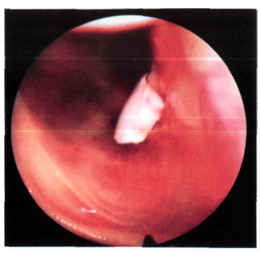

У больных с отрывом костно-хря-щевого фрагмента отмечаются периодические блокады травмированного сустава, наличие болевого симптома и выпота в полость сустава (рис. 32-1).

Р. с 32-1. Костно-хрящевой фрагмент в полоскости коленного сустава